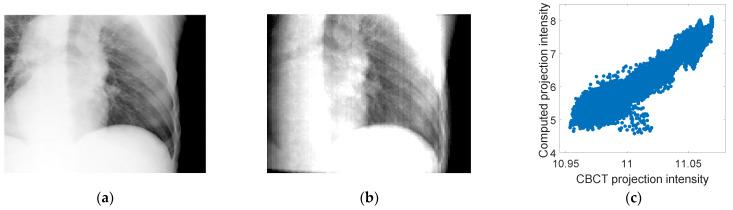

A method for generating fluoroscopic (time-varying) volumetric images using patient-specific motion models derived from four-dimensional cone-beam CT (4D-CBCT) images was developed. 4D-CBCT images acquired immediately prior to treatment have the potential to accurately represent patient anatomy and respiration during treatment. Fluoroscopic 3D image estimation is performed in two steps: (1) deriving motion models and (2) optimization. To derive motion models, every phase in a 4D-CBCT set is registered to a reference phase chosen from the same set using deformable image registration (DIR). Principal components analysis (PCA) is used to reduce the dimensionality of the displacement vector fields (DVFs) resulting from DIR into a few vectors representing organ motion found in the DVFs. The PCA motion models are optimized iteratively by comparing a cone-beam CT (CBCT) projection to a simulated projection computed from both the motion model and a reference 4D-CBCT phase, resulting in a sequence of fluoroscopic 3D images. Patient datasets were used to evaluate the method by estimating the tumor location in the generated images compared to manually defined ground truth positions. Experimental results showed that the average tumor mean absolute error (MAE) along the superior-inferior (SI) direction and the 95th percentile in two patient datasets were 2.29 and 5.79 mm for patient 1, and 1.89 and 4.82 mm for patient 2. This study demonstrated the feasibility of deriving 4D-CBCT-based PCA motion models that have the potential to account for the 3D non-rigid patient motion and localize tumors and other patient anatomical structures on the day of treatment.

开发了一种使用从四维锥形束CT(4D-CBCT)图像导出的患者特定运动模型来生成荧光透视(随时间变化)体积图像的方法。在治疗前立即采集的4D-CBCT图像有可能准确地反映治疗期间患者的解剖结构和呼吸情况。荧光透视三维图像估计分两步进行:(1)推导运动模型和(2)优化。为了推导运动模型,使用可变形图像配准(DIR)将4D-CBCT集中的每个相位配准到从同一集中选择的参考相位。主成分分析(PCA)用于将DIR产生的位移向量场(DVF)的维度降低为几个表示DVF中发现的器官运动的向量。通过将锥形束CT(CBCT)投影与从运动模型和参考4D-CBCT相位计算出的模拟投影进行比较,对PCA运动模型进行迭代优化,从而生成一系列荧光透视三维图像。使用患者数据集通过将生成图像中的肿瘤位置与手动定义的真实位置进行比较来评估该方法。实验结果表明,在两个患者数据集中,患者1沿上下(SI)方向的平均肿瘤平均绝对误差(MAE)和第95百分位数分别为2.29和5.79毫米,患者2为1.89和4.82毫米。这项研究证明了推导基于4D-CBCT的PCA运动模型的可行性,该模型有可能考虑三维非刚性患者运动,并在治疗当天对肿瘤和其他患者解剖结构进行定位。